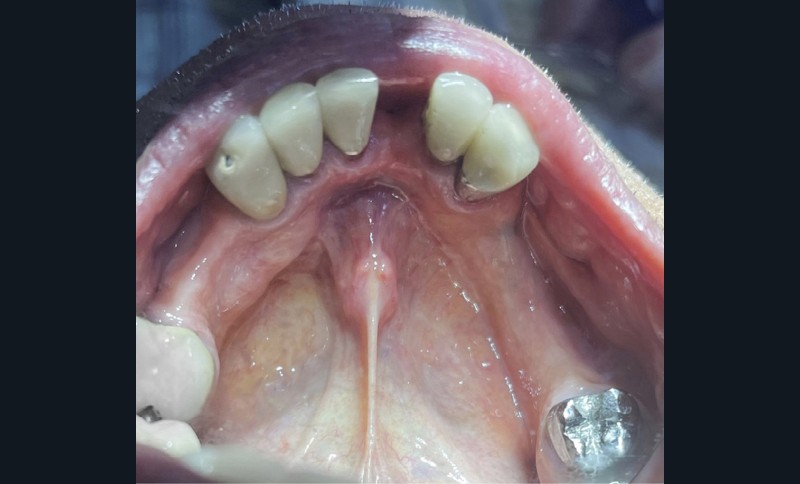

à l’examen endo-buccal, le patient présente un édentement de classe II de Kennedy modification 1, compensé par une prothèse amovible partielle composite en cobalt-chrome (fig. 1a et 1b). On note la présence de glissières de semi-précision parallèles PDC II (Afinor) entre 14-15 et entre 23-24, apportant guidage, stabilisation, sustentation et rétention par effet de coin. Au niveau mandibulaire, le patient présente un édentement de classe III modification 2 avec des crêtes de classe 3 selon la classification de Cawood et Howell, associées à une muqueuse ferme et adhérente (fig. 1c). L’insertion du frein lingual et labial, ainsi que des brides musculaires sont à distance. On note la présence de couronnes fraisées en 38 et en 46, l’absence de lésions apicales actives à l’examen radiographique (fig. 2), et une mésioversion de la 38 prenant la place de la 37.